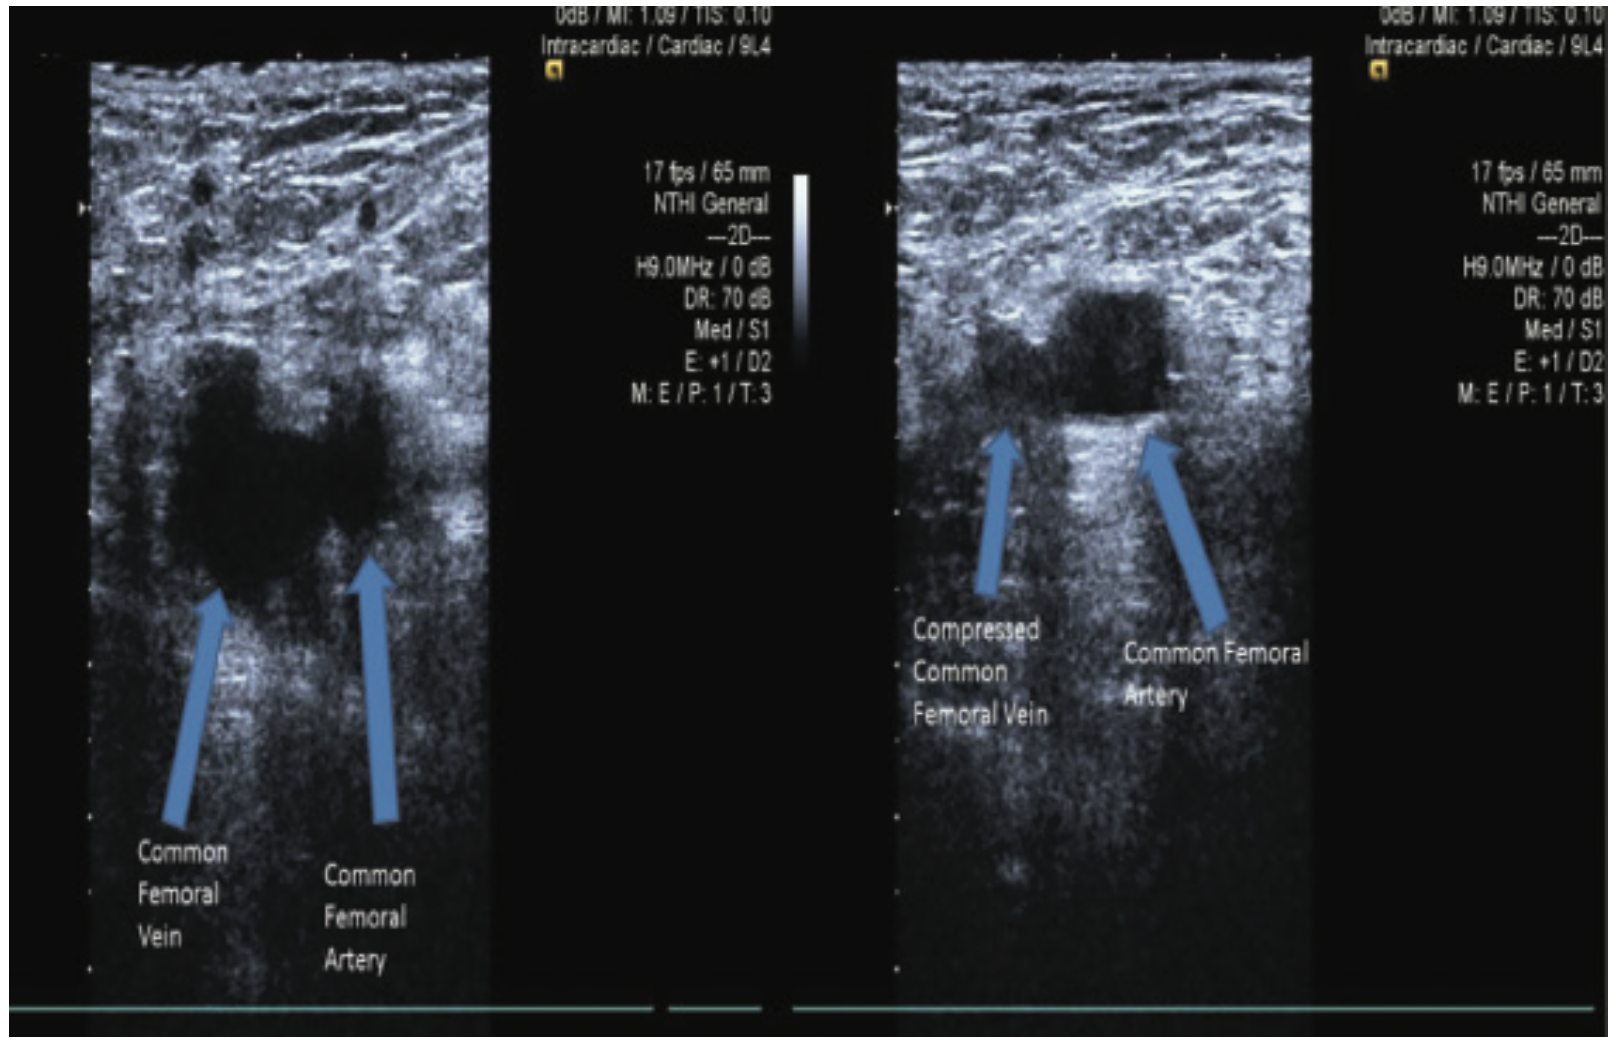

The Anatomy of Femoral Vascular Access — Taming the SRU

From www.tamingthesru.com

The Anatomy of Femoral Vascular Access — Taming the SRU Cut Down Vascular Access Learn how to perform it, what equipment is needed, and what complications may arise. The venous cutdown technique is a surgical procedure designed to gain venous access when relatively less invasive. A cutdown procedure gives the physician access to the saphenous or antecubital vein. Learn about the technique of venous cutdown, which involves making an incision in the saphenous vein. Cut Down Vascular Access.